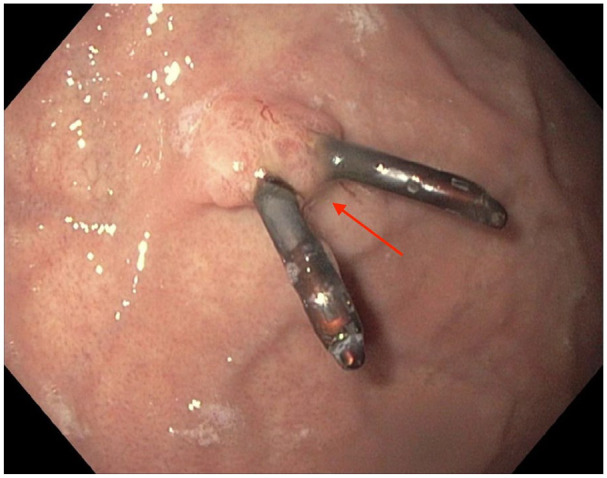

Oxyntic gland adenomas (OGAs) are benign gastric neoplasms composed of gland-forming epithelial cells with predominantly chief cell differentiation resembling oxyntic glands confined to the mucosa. If the tumor has submucosal invasion, it should be classified as gastric adenocarcinoma of fundic gland type. The OGAs can pose a diagnostic challenge, as they can resemble aggressive gastric neoplasms. There are no current guidelines on the management of OGA. Due to the relatively small size and low malignant potential, these lesions are typically managed endoscopically. In this case, we are reporting a 22-year-old woman who was diagnosed with OGA during evaluation of iron deficiency anemia and underwent successful endoscopic resection.